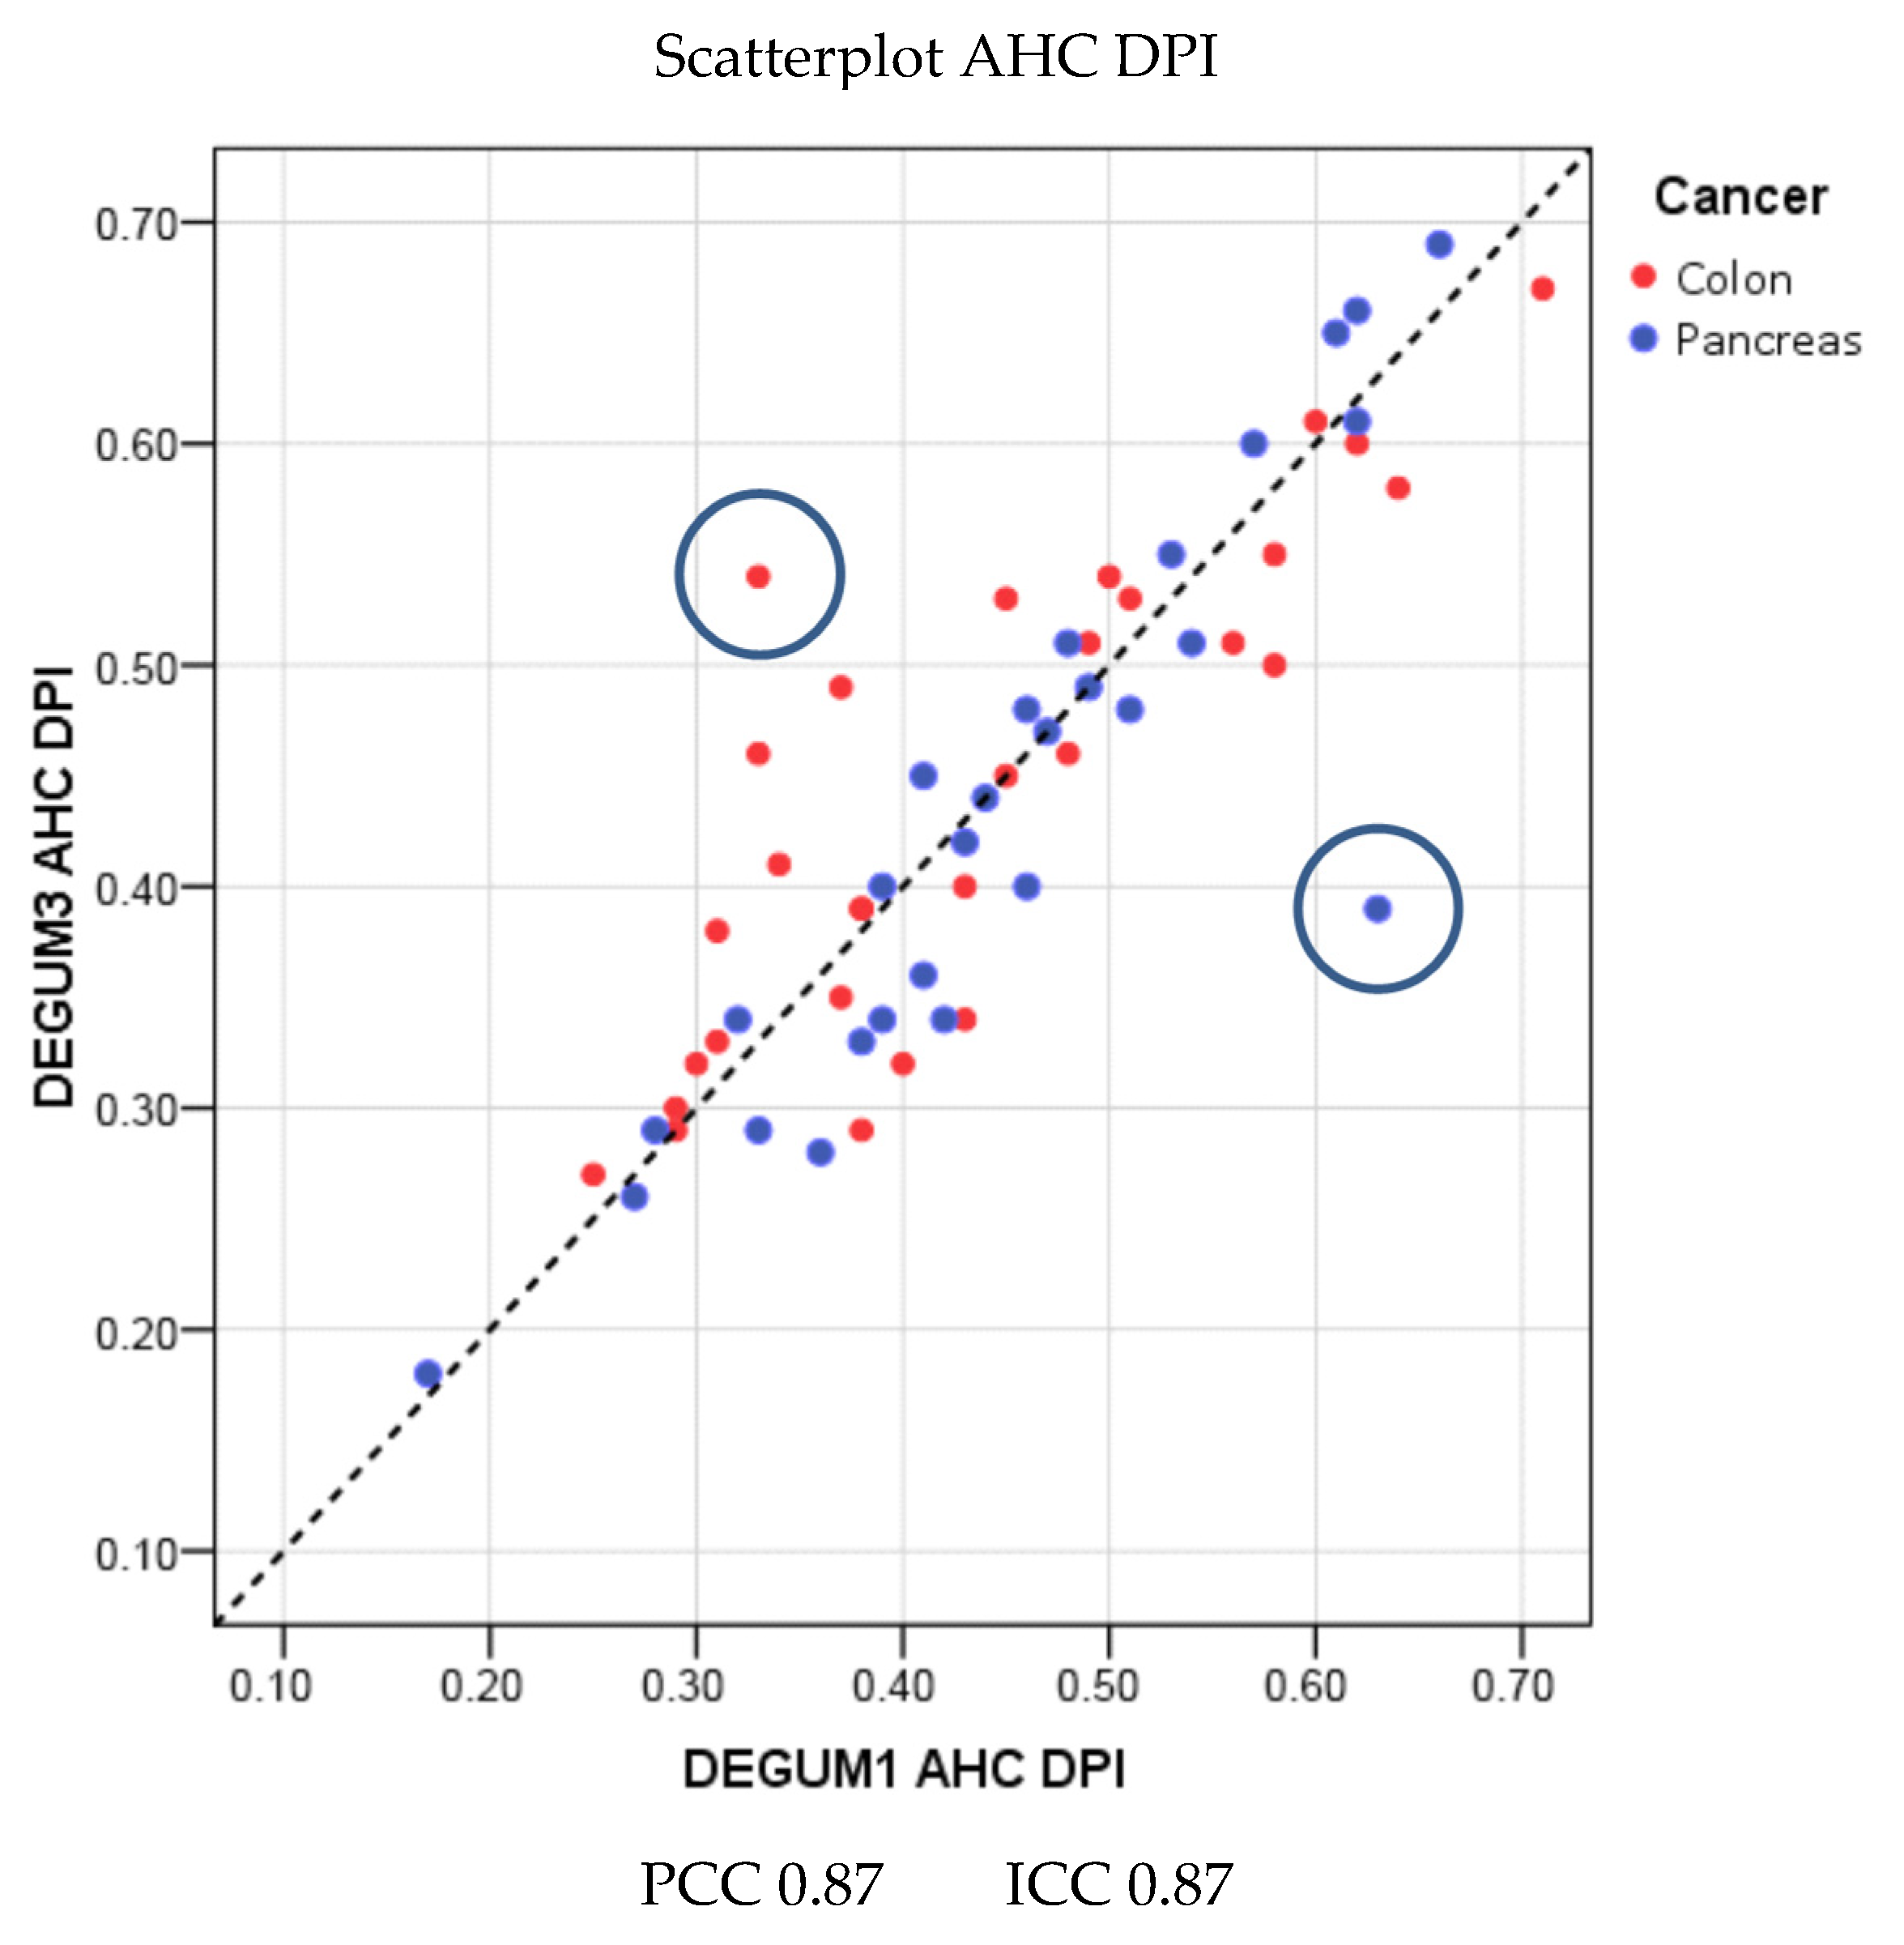

| Parameter | Diameter [mm] | Insonation Angle | Doppler Shift [cm/s] | Flow [mL/min] | AHP-DPI |

|---|---|---|---|---|---|

| N | 79 | 76 | 76 | 76 | 76 |

| Mean D1 (SD) | 4.4 (0.7) | 35.8 (16.9) | 24.6 (11.3) | 308 (165) | 0.3 (0.1) |

| Mean D3 (SD) | 4.5 (0.7) | 36.6 (17.3) | 25 (9.4) | 332 (166) | 0.3 (0.1) |

| Mean tot (SD) | 4.5 (0.7) | 36.2 (17) | 24.8 (10.3) | 320 (165) | 0.3 (0.1) |

| Mean Diff (SD) | 0.1 (0.4) | 0.8 (14.9) | 0.5 (8.5) | 24 (86) | 0.01 (0.05) |

| p(Bias) | 0.10 | 0.98 | 0.14 | 0.05 | 0.06 |

| p(Var) | 0.38 | 0.33 | 0.25 | 0.94 | 0.66 |

| PCC | 0.81 | 0.62 | 0.68 | 0.87 | 0.90 |

| ICC (95% CI) | 0.81 (0.71; 0.87) | 0.62 (0.46; 0.74) | 0.67 (0.52; 0.78) | 0.86 (0.78; 0.91) | 0.90 (0.84; 0.93) |

| MVC | 0.05 | 0.27 | 0.15 | 0.13 | 0.08 |

| B/A Limits | (−0.79; 0.94) | (−28.5; 30.1) | (−16.1; 17.0) | (−145; 192) | (−0.09; 0.11) |